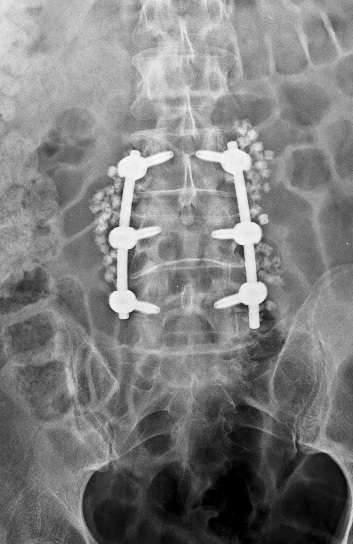

Cirugía de mínima invasión y microcirugía

La cirugía de mínima invasión y la microcirugía son técnicas quirúrgicas avanzadas que permiten tratar diversas afecciones de la columna con menor daño a los tejidos.

A través de incisiones pequeñas y el uso de instrumentos especializados y tecnología de alta precisión, se busca reducir el dolor postoperatorio, el sangrado y el tiempo de recuperación. Nuestras técnicas ofrecen resultados efectivos y mayor seguridad para ti como nuestro paciente, permitiendo una reincorporación más rápida a tus actividades diarias, siempre que se realicen bajo una adecuada valoración médica.